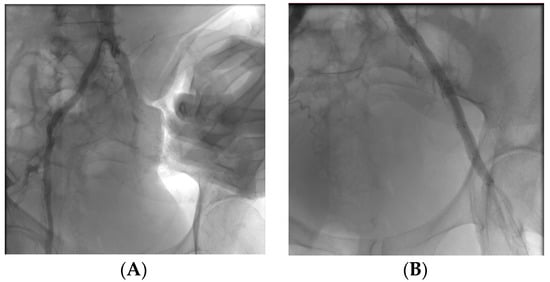

A 78-year-old patient is admitted to nephrology for dialysis. While attempting to place a CVC for haemodialysis in the right laterocervical region, there is a pulsating swelling on the neck. On ECD a pseudoaneurysm of about 4 cm is detected, fed by a small breach on the common carotid artery in the lateral region. A CT angiogram was performed, which confirmed the presence of the pseudoaneurysm at the middle III of the common carotid artery with a leak of contrast medium from the same at the site of a previous accidental puncture. Verifying the risk of suffocation due to accumulation of blood at the base of the neck, an urgent surgical intervention is performed by placing a COVERA PLUS stent (9 × 60 mm) to block the breach in the carotid artery. Intra-operative and post-operative angiographic control is performed to detect the perviousness of the vessels downstream of the stent and downstream of the right carotid bifurcation. After the endovascular treatment, a surgical cut is made in the vicinity of the haematoma created to allow the blood to flow out and the pouch to empty.

Figure A2. Intra-operative (A) and post-operative (B) angiogram.